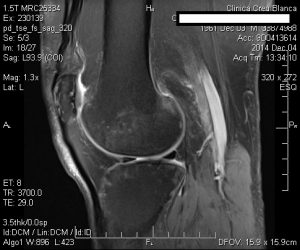

La mejoría sintomática fué casi inmediata y la evolución se hizo evidente en la RM el 4/12/2014, en menos de dos meses de realizado el tratamiento con implantes de oro. El paciente tenía unas perspectivas (según los médicos tratantes) de una baja laboral de muchos meses, con una gran incertidumbre respecto a su futuro laboral, y con un pronóstico incierto de su capacidad laboral.

Fué dado de alta el 31/12/2014 reintegrándose a su actividad laboral habitual (jornada completa en bipedestación y marcha). Realiza controles clínicos periódicos. La evolución es excelente.

A continuacion se observan las imágenes más significativas: